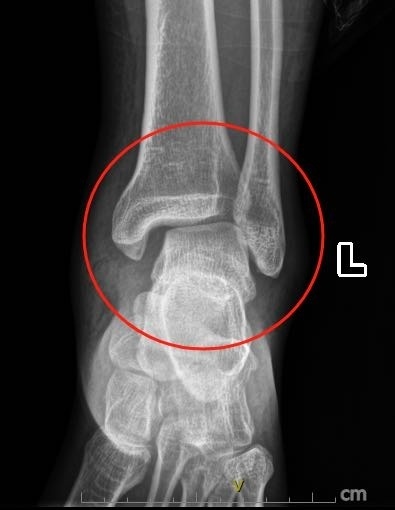

男子踩空台阶崴脚没重视险致残医生扭伤脚脖子别仅凭感觉判断轻重

崴脚后一直疼痛怎么判断是脚踝拉伤扭伤还是骨折